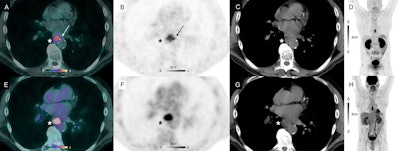

Ga-68 NODAGA-RGD-PET/CT (A), PET (B, D) and CT (C) and F-18 FDG-PET/CT (E), PET (F, H) and CT (G) axial views of a primary lesion (asterisks) in a 53-year-old participant with esophageal squamous cell carcinoma. Note intense homogenous uptake in the primary lesion on F-18 FDG-PET/CT (SUVmax 12.1 g/mL, metabolic tumor volume 2.54 cm3), whereas the primary lesion demonstrates a different uptake pattern in the corresponding Ga-68 NODAGA-RGD-PET/CT image: a weaker and more heterogeneous uptake (SUVmax 5.1 g/mL), seen mostly in the periphery of the tumor, with a slight extension in perilesional structures (arrows), and a larger metabolic tumor volume (metabolic tumor volume 5.35 cm3). Image courtesy of the European Journal of Hybrid Imaging through CC BY 4.0.Esophageal cancer is the seventh most common cancer worldwide and accounts for more than half a million deaths each year. F-18 FDG-PET/CT detects tumors in these patients by visualizing abnormal tumor glucose metabolism, yet Ga-68 NODAGA-RGD PET/CT targets different tumor activity, the researchers explained.

However, the researchers noted that while F-18 FDG uptake was homogenous inside all the confirmed primary sites (n = 9), Ga-68 NODAGA-RGD showed more heterogenous uptake in six out of the nine confirmed primary sites (67%). These sites were involved in potential early angiogenesis, with activity on imaging seen mostly in the periphery of the tumor and extending into surrounding tissue in five out of the nine confirmed primary sites (56%), they wrote.